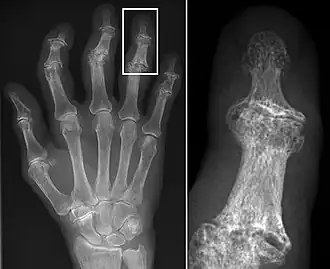

Osteoarthritis

Osteoarthritis (OA) is a degenerative joint disease that affects the junctions of articulating elements, or synovial joints (e.g. knee, shoulder) and is characterized by the damage of cartilage. OA is the most commonly documented pathology found in archaeological human remains and has been used extensively as an activity marker that reflects stress-related activity patterns or occupation.[11] Factors such as age, sex, body size and others also affect its expression.[12]

Kathryn Marklein from the Ohio State University explored the prevalence of OA between two Roman period (2nd – 3rd c. CE) skeletal assemblages retrieved from mass graves in Oymaağaç, Vezirköprü, Turkey. It was previously indicated through the analyses of non-metric traits that several individuals from one of the mass graves demonstrated biological relatedness with each other. In order to establish an approach for the evaluation of a possible genetic and socio-historical context correlated with OA, Marklein’s aim was to test if comparing different OA distribution patterns between familial and non-familial groups can indicate familial relatedness at Oymaağaç. Ten synovial joints were selected for the study among adults from site 1 (17 individuals) and site 2 (23 individuals). The study found no significant data to suggest a correlation between OA and different burial group, nor a correlation between OA and biologically related individuals.[13]